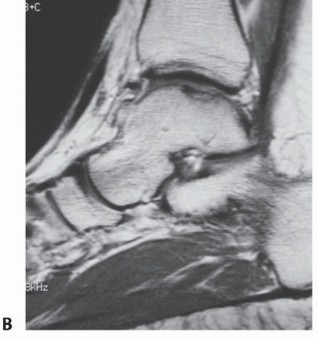

Stage III: articular cartilage breached, high signal changes behind fragment indicating synovial fluid between fragment and underlying subchondral bone (FIG 1)

FIG 1 • A. Arthroscopic view of a full-thickness osteochondral defect at the talar dome. B. Corresponding MRI.*